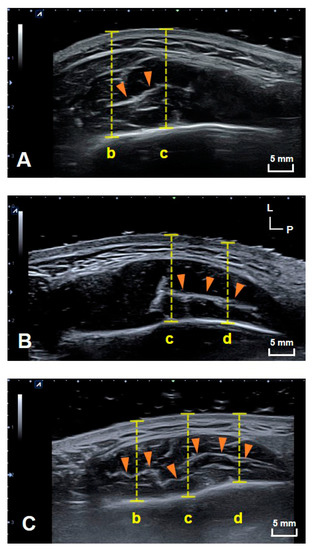

US images of the DIT of the masseter muscle were obtained in all subjects on both sides. The structural patterns of the DIT were classified into three different types. Type A covered reference lines b and c (anterior two-thirds of the masseter muscle); type B covered reference lines c and d (posterior two-thirds of the masseter muscle); and type C covered reference lines b, c and d (most of the inferior part of the masseter muscle). Figure 1 shows example images of DITs with structural patterns of types A (21.8%, n = 7), B (9.4%, n = 3) and C (68.8%, n = 22). The DIT could be detected more easily on longitudinal images than transverse images. The classification into the three tendon types did not differ significantly with sex, age, or left and right sides.

Figure 1.

Transverse US images showing the three patterns of the DIT. US images of (A) types A, (B) B and (C) C. (b) The line halfway between the anterior border of the masseter muscle and line c, (c) the line halfway between the anterior and posterior borders of the masseter muscle, and (d) the line halfway between line c and posterior border of the masseter muscle. The yellow dashed lines indicate the depth from the skin surface to the mandible. L, lateral; P, posterior; orange arrowheads, DIT.

The present study used US to verify the structural patterns of the DIT of the masseter muscle in healthy young volunteers and compared the findings with those obtained in previous cadaver dissections. Performing US scanning at the same sites as in the cadaveric study has clearly revealed the structural patterns of the DIT. Furthermore, the structural pattern of the DIT was classified into three types: Type A covered references lines b and c (anterior two-thirds of the masseter muscle); type B covered reference lines c and d (posterior two-thirds of the masseter muscle); and type C covered reference lines b, c and d (most of the inferior part of the masseter muscle) (Figure 1).